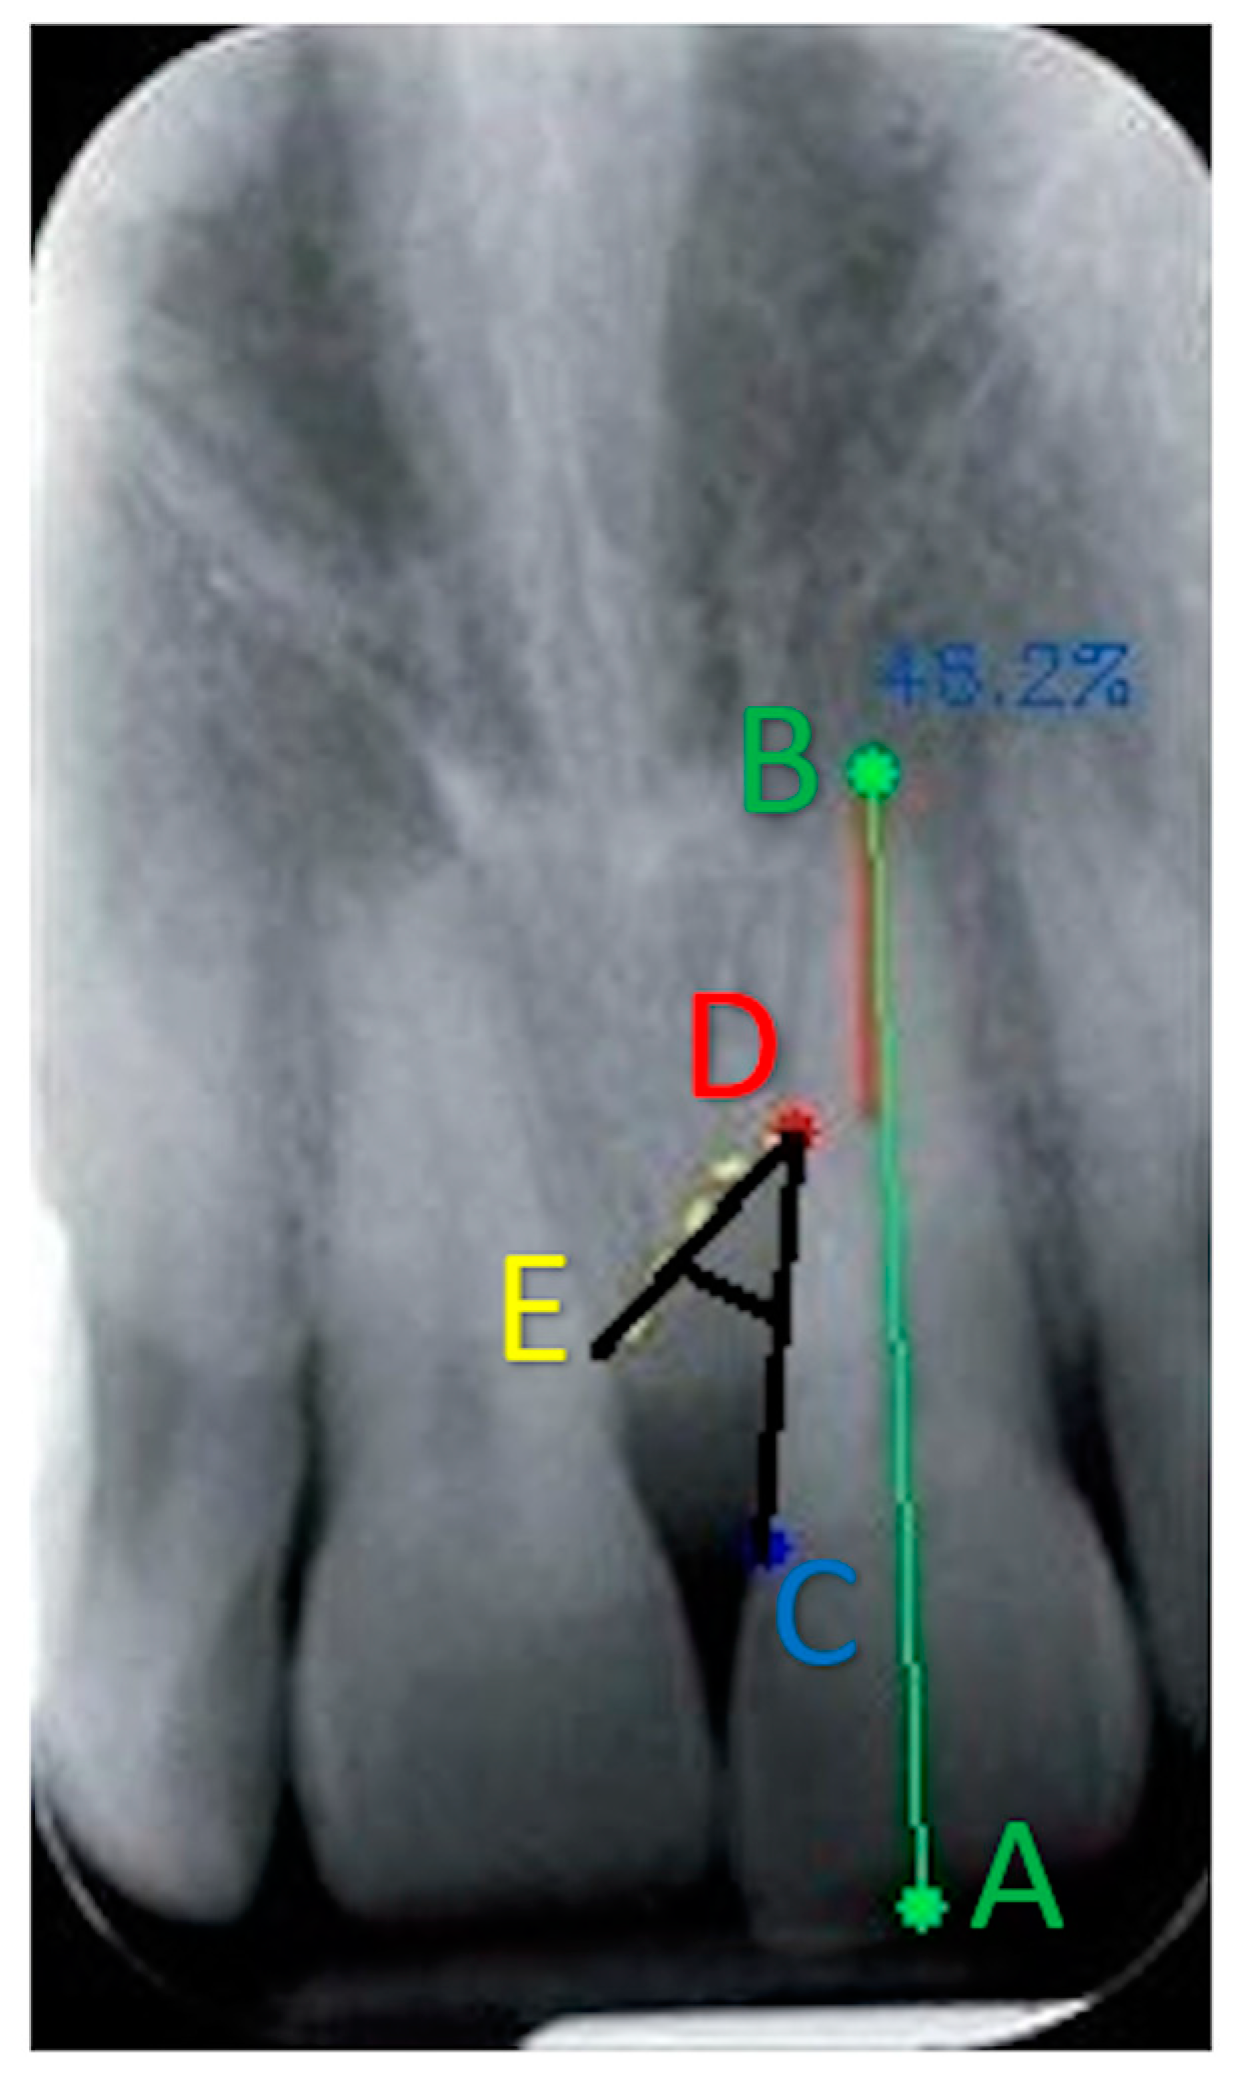

2.4. BDA Software

- Point A: coronal margin;

- Point B: root apex;

- Point C: enamel–cement junction (CEJ) of the tooth involved in the intraosseous defect (constant reference point), which can be identified in the radiographic image by the difference in radiopacity of the enamel compared to the cement or by their variation in intensity since the enamel is radiopaque compared to the cement. If restorations are present, the apical margin of the restoration is used to replace the CEJ as a fixed reference point;

- Point D: the most apical point of the angular defect (bottom of the defect).